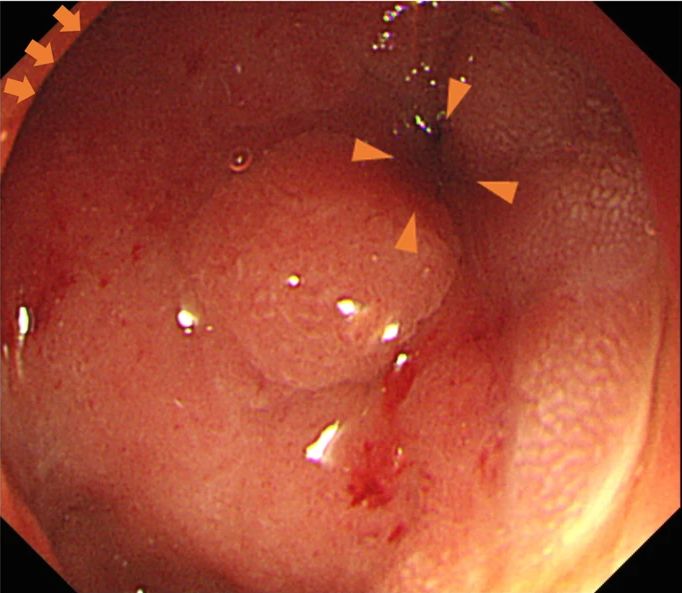

血清肿瘤标记物,如碳水化合物抗原(CA) 19-9、CA 125、α-fetoprotein (AFP)、癌胚抗原(CEA)均在正常范围内。食管胃十二指肠镜检查(EGD)显示粘膜下肿瘤样病变,累及十二指肠球部整个圆周,表面光滑,界线不清(图1)。由于十二指肠狭窄,故内镜无法通过十二指肠球部。

图1 EGD检查显示十二指肠球部梗阻。箭头:幽门环;三角箭头:十二指肠球部梗阻